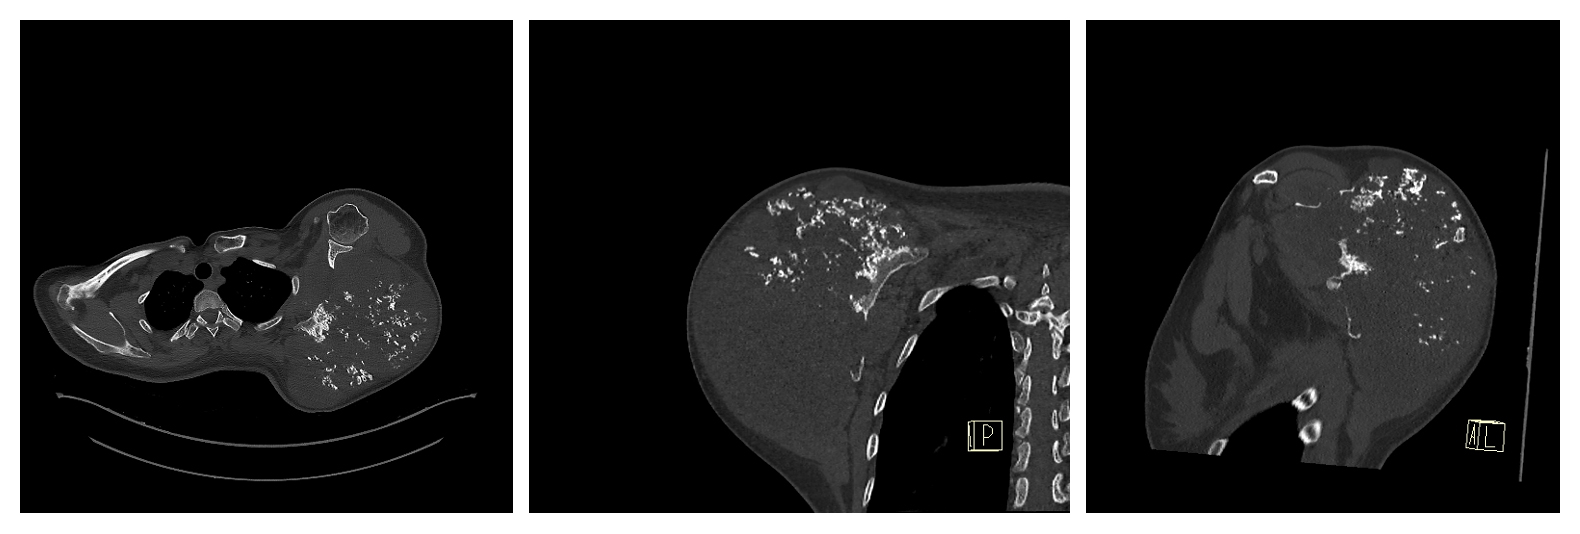

Ameliyat Öncesi: Tomografide skapulada destrüksiyon görünmekte.

Ameliyat Öncesi: MR’da tümörün heterojen olup nekroz alanları içerdiği görünmekte.